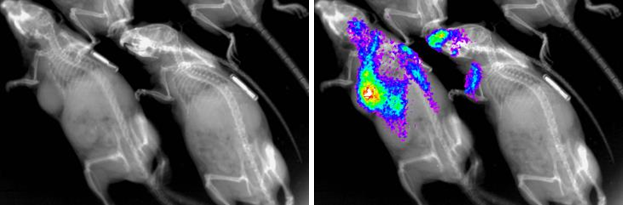

InVivo Imager (2D X-Ray, fluorescence/luminescence)

IVIS Lumina X5

- Acquire 2D X-Ray, Fluorescence, Luminescent images

- Track labeled cells/tumors

- Quantify Size/Intensity